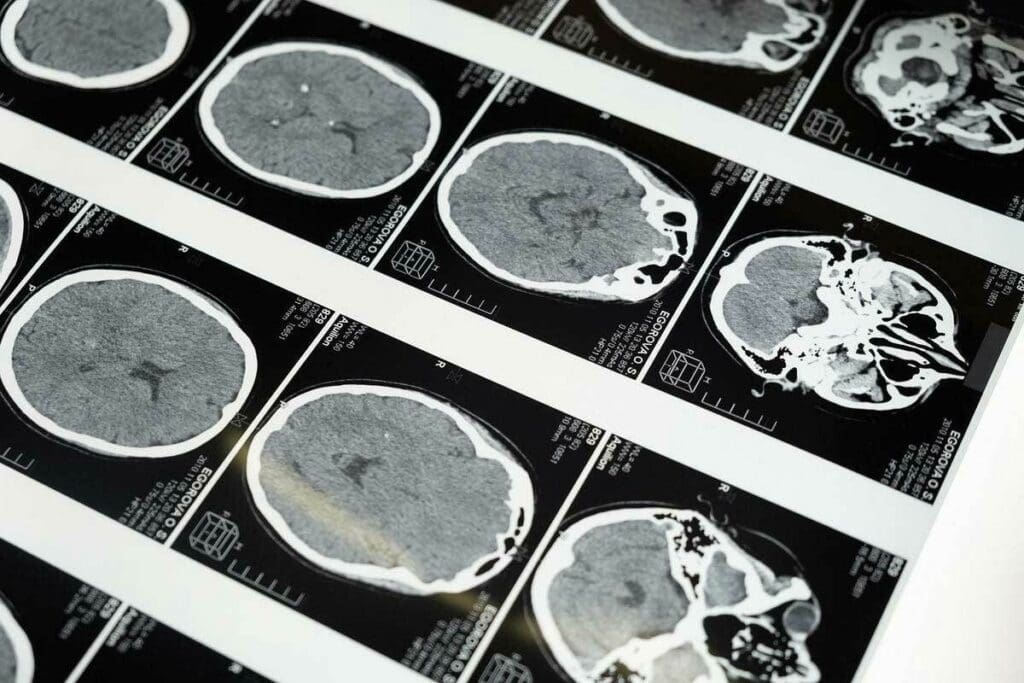

Imaging Tests Used to Detect Brain Tumors

Imaging tests are key in finding brain tumors. MRI and CT scans are the most commonly used. MRI shows soft tissue tumors well. CT scans are faster and good for emergencies.

| Imaging Test | Primary Use | Benefits |

| MRI | Soft tissue tumor visualization | High-resolution images, detailed anatomy |

| CT Scan | Emergencies, calcification detection | Quick, sensitive to acute hemorrhage |